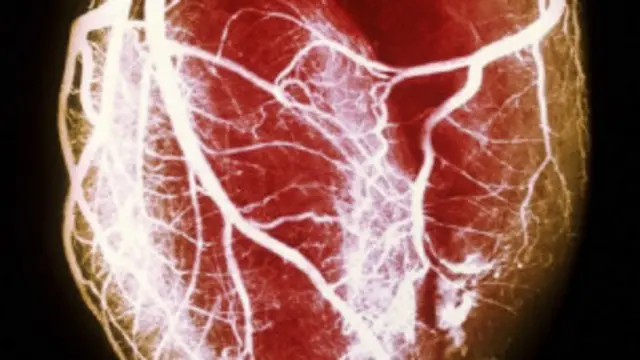

इमेज स्रोत, SCIENCE PHOTO LIBRARY

जिन महिलाओं का एक बार तलाक हुआ है, उनमें से 24 फ़ीसदी को हार्ट अटैक का ख़तरा रहा है जबकि शादी में बने रहने वाली महिलाओं में इसका ख़तरा नहीं था.

जिन महिलाओं का कई बार तलाक हो चुका है, उनमें इसका ख़तरा 77 फीसदी तक रहता है.

पुरुषों के मामले में ये ख़तरा 10 फीसदी तक रहता है जबकि एक से अधिक तलाक के मामलों में ख़तरा 30 फीसदी तक बढ़ जाता है.